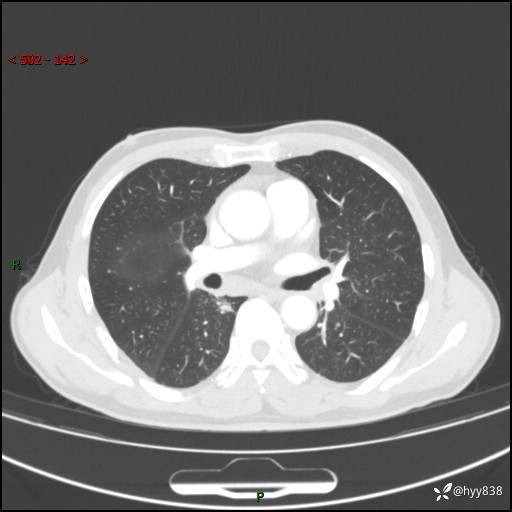

69岁/男,发现肺部病变6天。该有的征象都有,肉芽肿 VS 肿瘤,一念之间---(有结果)

主诉:发现肺部病变6天。

现病史:患者6天前于我院泌尿外科住院,住院期间行胸部CT检查,提示“肺部病变”,患者无畏寒、发热、盗汗、咳嗽、咳痰、咯血、胸痛、呼吸困难,无反酸、腹痛、腹泻、头痛、头晕等不适。未予特殊处理,现为进一步诊治,门诊以“肺肿物”收入我科。 患者本次起病以来,精神食欲尚可,大小便正常,体力及体重无明显变化。

胸部CT平扫+增强